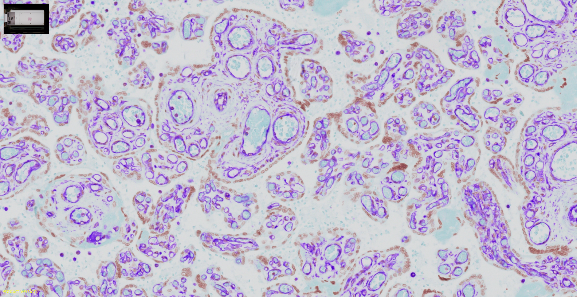

清晰捕捉各种组织和染色的细节

胎盘波形蛋白(Vimentin)的免疫组化染色(IHC)